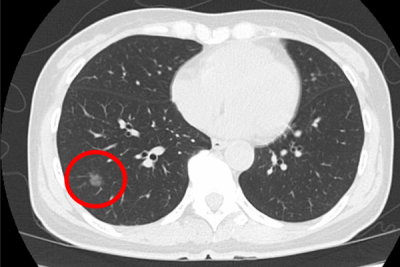

胸腔鏡下手術の創部は2cm程度であり、以前のように創からの腫瘤の触知は困難です。そこで、場所の特定(腫瘍がどこにあるか)を確認するために、術前マーキングという方法がとられています。方法としては、(1)経皮的にフック型の“針”を留置(2) “色素”注入(3)気管支鏡下に“造影剤”注入(4) “蛍光”気管支鏡などです。デメリットとして、機器が特殊で高額であるため施設が限定される、気胸や塞栓の合併症、術前の局所麻酔下の処置であり手術前の患者さまの負担になること等が挙げられます。特に、肺や気管支への穿刺は、空気塞栓等致死的合併症の可能性があり、すでに裁判例もあります。

術中CTマーキング法

そこで当科では、ハイブリッド手術室を利用した術中CTマーキングを行っています(佐賀の病院に引き続き全国2施設目に導入)。手術中に、CT-like imageを作成し場所を特定します。そして悪性であれば、そのままがんの手術を行います。特徴として、全身麻酔下に手術室で完遂するため、手術までに気管支鏡やCTガイド下肺生検などの苦痛がないこと、局在の指摘精度が高いこと、致死的な肺空気塞栓症を回避できること等が挙げられ、患者さんにも、我々医療者にもメリットがあります。国内では、ハイブリッド手術室のない施設が大半であり、このマーキングが利用できる施設は限られています。

当科では、2014年9月より、ハイブリッドマーキングを施行しており、患者さまの術前の負担なく、正確な診断ができ、悪性であればそのままがんの手術を施行しています。1回の手術で診断も治療もできる患者さまに優しい方法です。

胸部CTでの肺小陰影画像

術中確認するCT画像